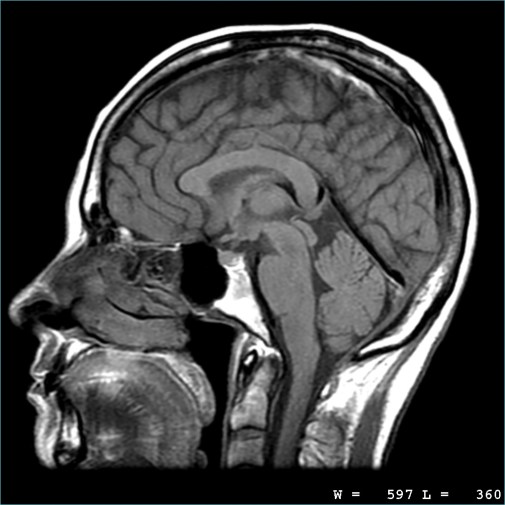

Most people will only ever see one of these MRI scans if there is a problem… but scientists have been using them more frequently over the last twenty years to study normal brain function and structure as well.